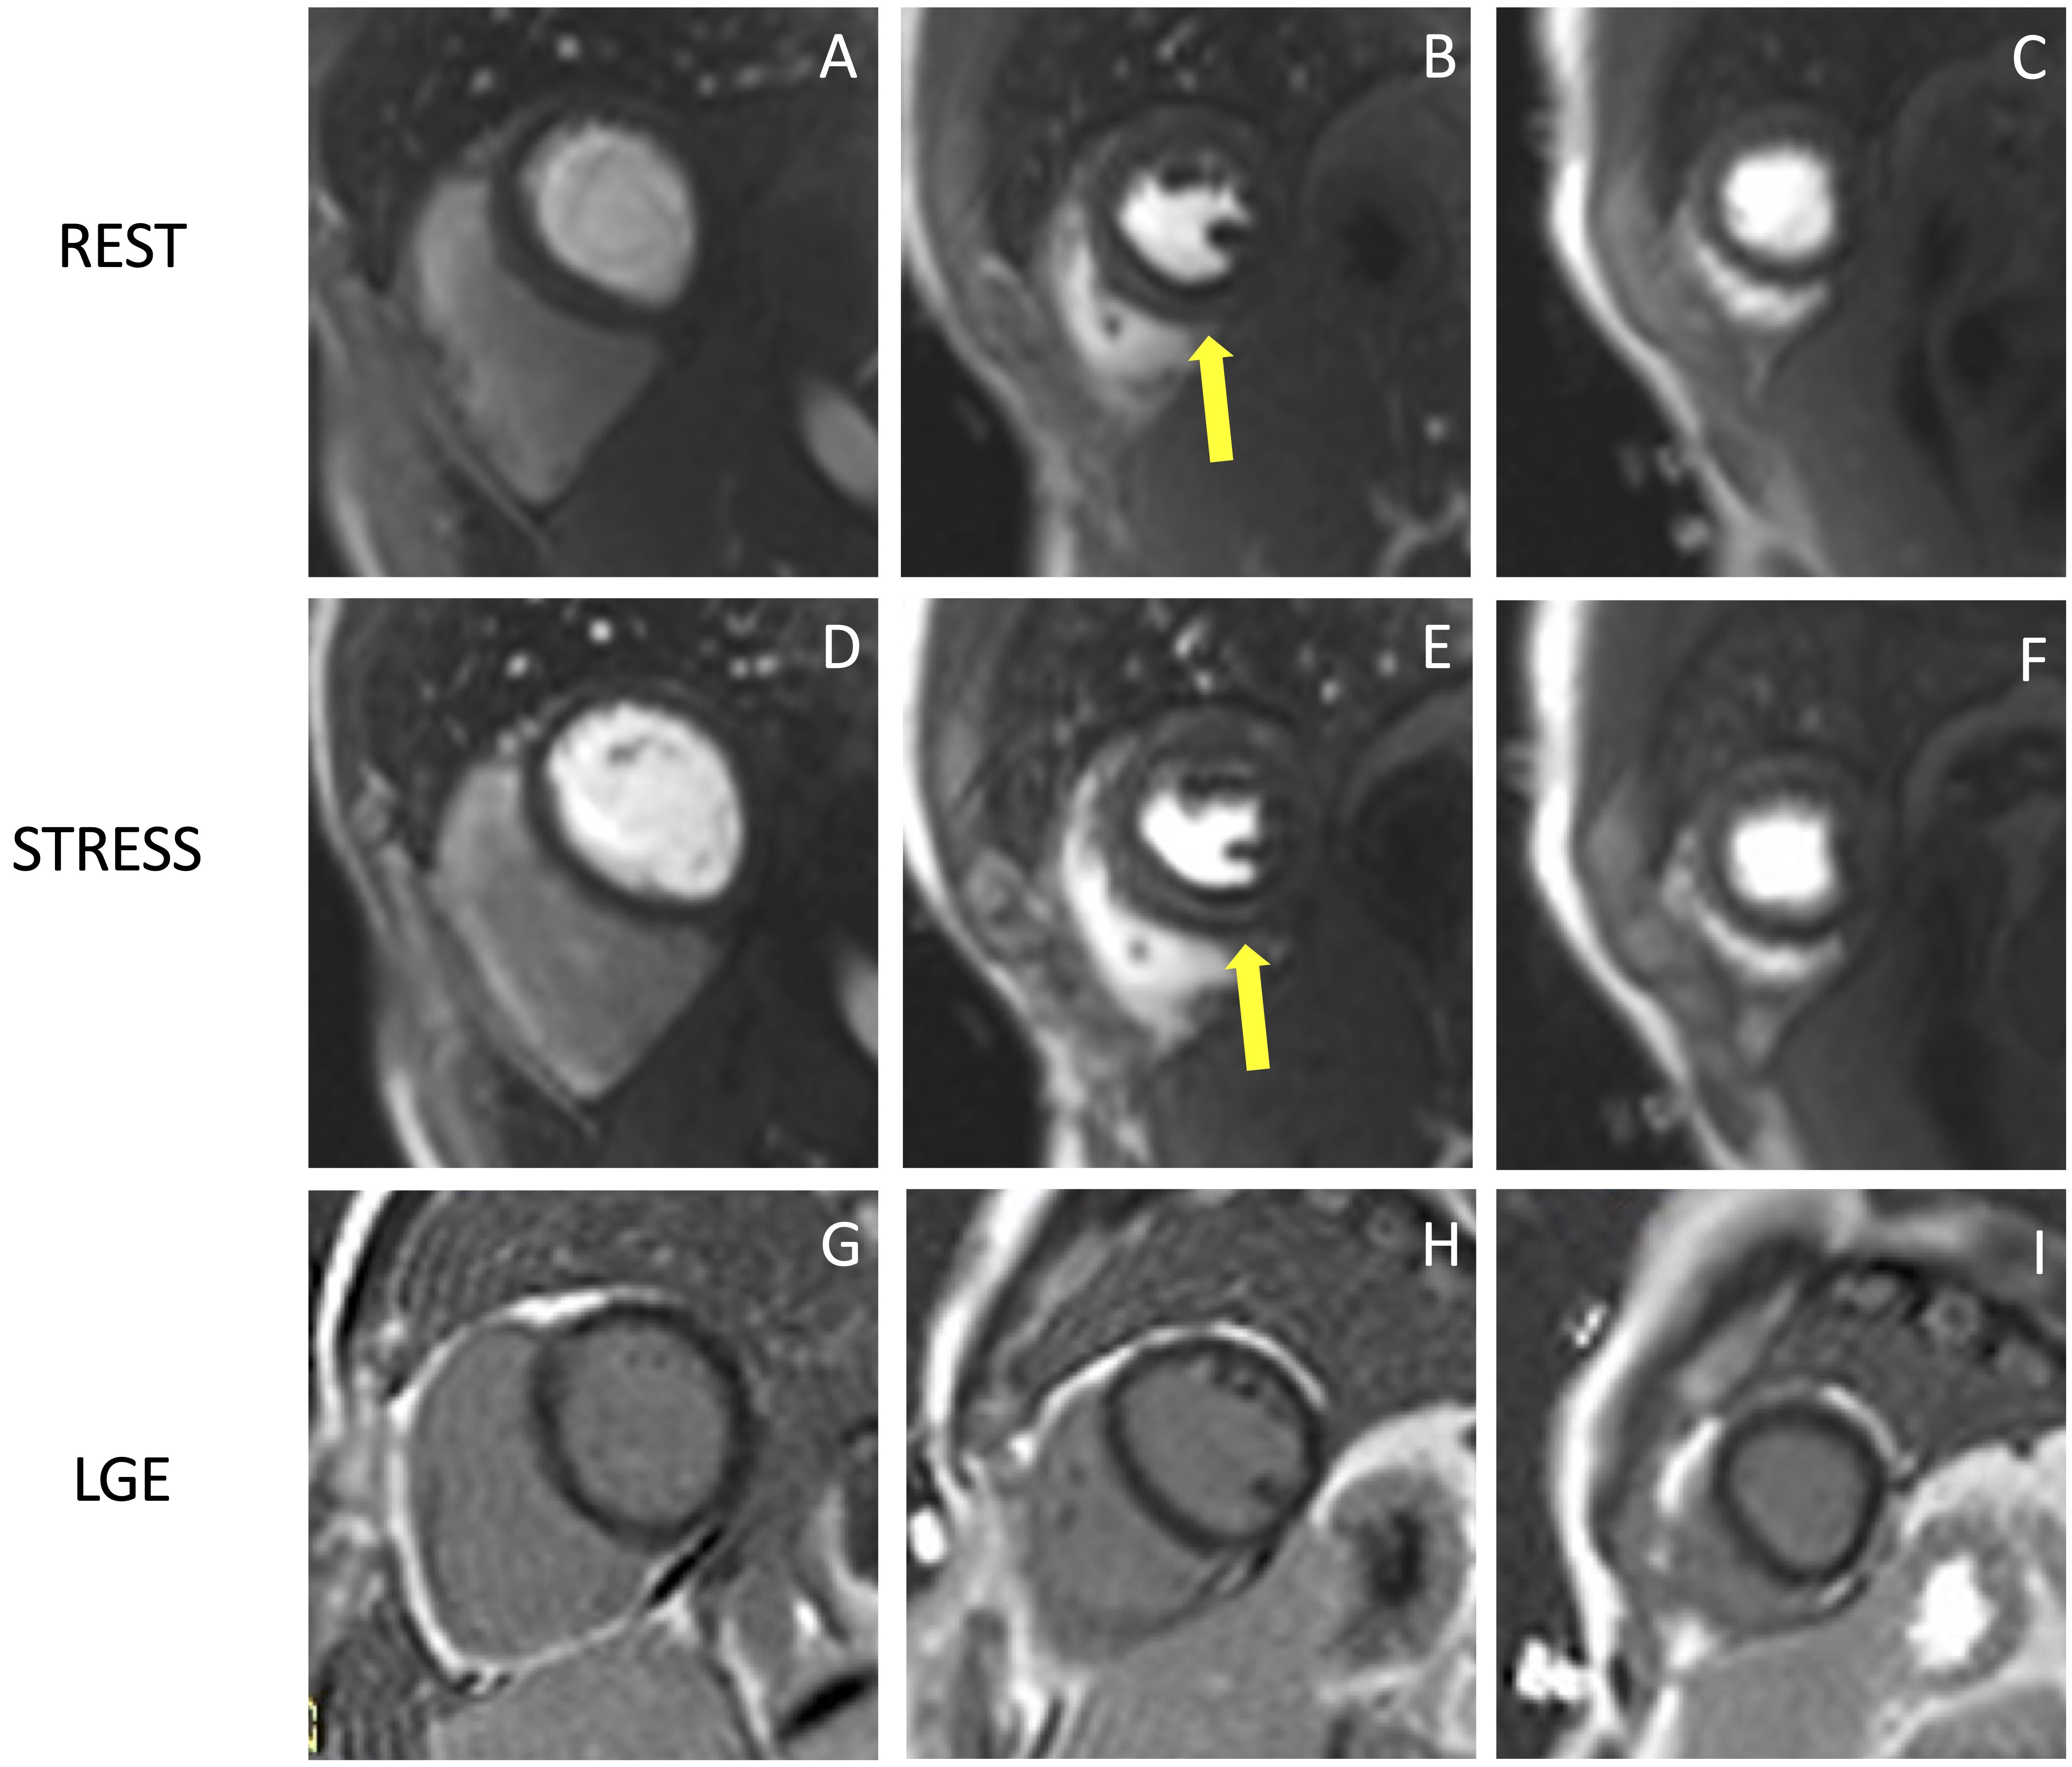

The perfusion images are analyzed using the American Heart Association (AHA) 16-segment model [29]. By assessing the number of segments with perfusion defects due to ischemia, the global ischemic burden can be estimated. The perfusion defect is usually most evident about three heart beats after the maximal contrast enhancement of the ventricular cavity and continues while the contrast washes out. It is important to distinguish inducible perfusion defects from artifacts. The most common is the ‘dark-rim artifact’, which appears as a hypointense area in the subendocardial layer of the myocardium, usually due to low spatial and temporal resolution (Fig. 3). Dark rim artifacts usually appear as the gadolinium first reaches the ventricular cavity, but it vanishes once the myocardium is enhanced. Moreover, they are present during both rest and stress conditions in the absence of underlying scars in the LGE images.

Fig. 3.

Fig. 3.Example of stress CMR images showing the ‘dark-rim artifact’. CMR adenosine-stress perfusion in a 44-year-old man with a known congenital coronary artery abnormality (RCA with a high take off and inter-arterial course). Short axis rest and stress perfusion images are shown respectively at the basal (A,D), mid-ventricular (B,E), and apical (C,F) levels. There is evidence of a transient hypointense area in the subendocardial layer of the mid-ventricular septal segments (yellow arrows) both in the rest and stress images (B,E), during the early phase of passage of GBCA bolus through the left ventricle, suggestive for “dark rim artifact”. Corresponding LGE images (G,H,I) show no myocardial scars. CMR, cardiovascular magnetic resonance; LGE, late gadolinium enhancement; RCA, right coronary artery; GBCA, gadolinium-based contrast agent.